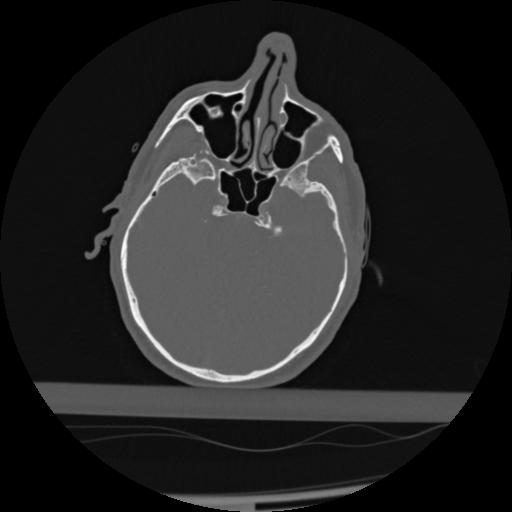

22 ANGIO,CE,Vol,0.5,ANGIO,,